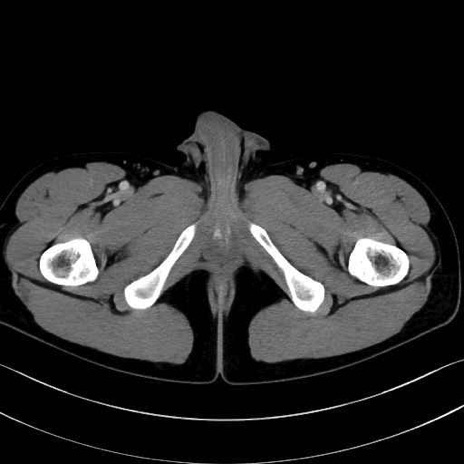

小殿筋 (Gluteus minimus)